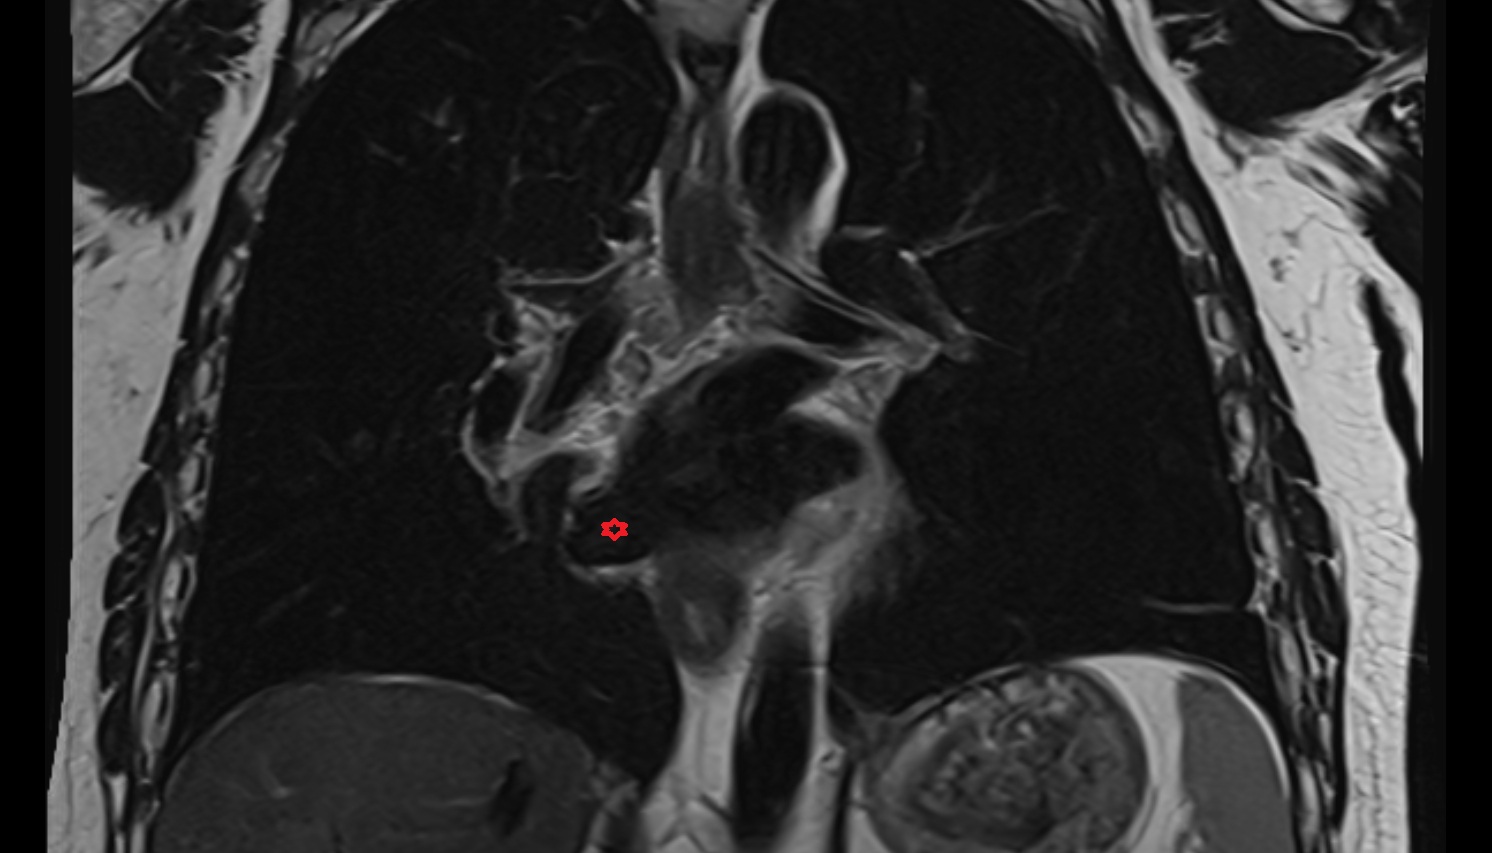

- Pituitary gland

- Pituitary stalk

- Anterior lobe of pituitary gland

- Posterior lobe pituitary gland

- Sella turcica